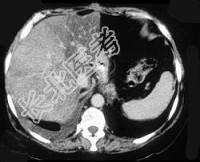

- 单项选择题男,66岁, 肥胖,有糖尿病史, CT检查如图,最可能的诊断是 ( )

A、局灶性脂肪肝

B、肝硬化肝癌

C、肝血管瘤

D、肝胆管细胞癌

E、肝淋巴管瘤